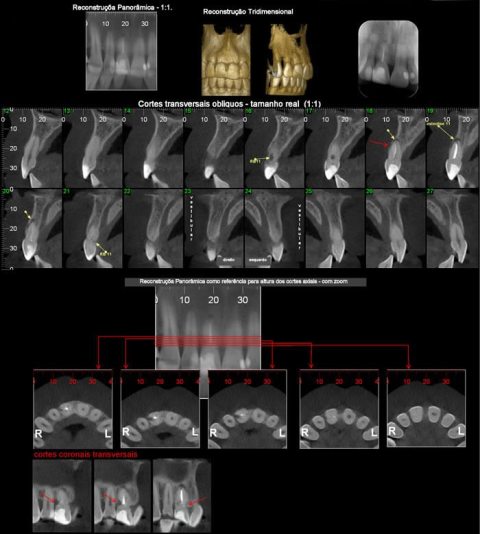

CASO 6 - Reabsorção

Achado radiográfico, na radiografia periapical de rotina, nota-se área de menor densidade na distal cervical e alteração no contorno na mesial, e rarefação óssea periapical. Ao exame tomográfico pode-se observar o dente 11 com osteólise apical e área de reabsorção na distal e reabsorção por substituição na mesial.

CASO 7 - Perda Óssea

Exame tomográfico de rotina para estudo de implante em áreas edêntulas posteriores. Observa-se perda da cortical vestibular no dente 41.